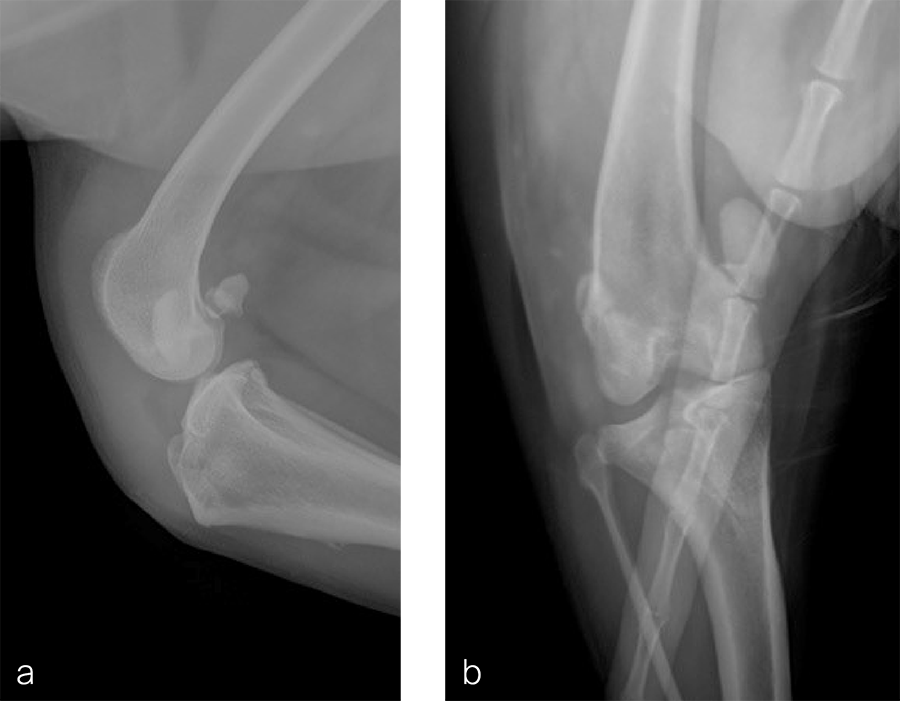

Fig 9a-b Preoperative CT 3D reconstruction of the right femur confirming distal femoral varus (anatomical Lateral Distal Femoral Angle was 104°). Planned correction was to perform a 10° lateral closing wedge ostectomy.